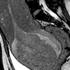

porod, snemanje, magnetna resonanca Sprednji pogled glave otroka v medeničnem vratu. Žurnal24 porod, snemanje, magnetna resonanca